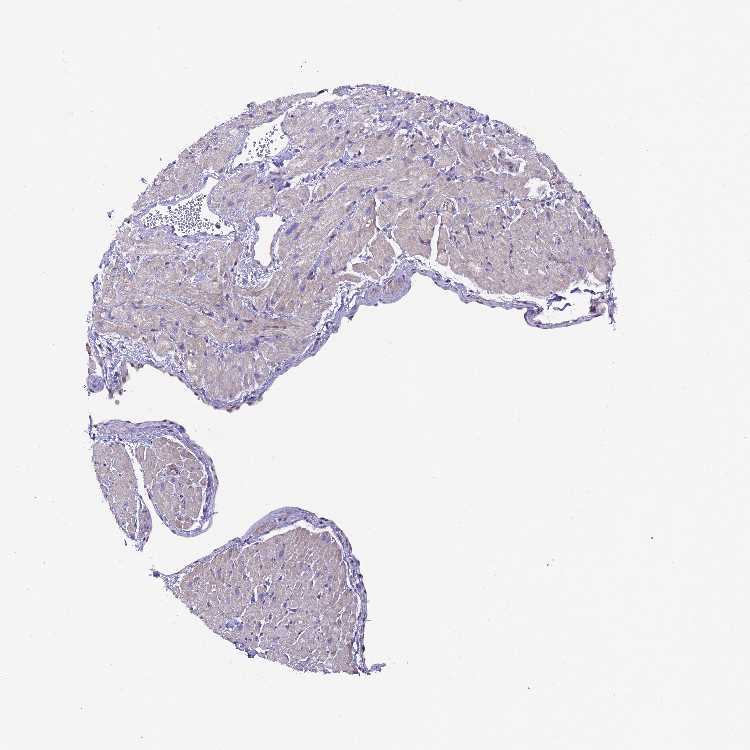

HEART MUSCLE - Antibody stainingi

Antibody staining in the annotated cell types in the current human tissue is reported as not detected, low, medium, or high, based on conventional immunohistochemistry profiling in selected tissues. This score is based on the combination of the staining intensity and fraction of stained cells.

Each image is clickable and will lead to virtual microscopy that enables deeper exploration of all samples and also displays staining intensity scores, fraction scores and subcellular localization as well as patient and tissue information for each sample.

Antibody HPA041706Antibody HPA046766

Cardiomyocytes Not detectedNot detected